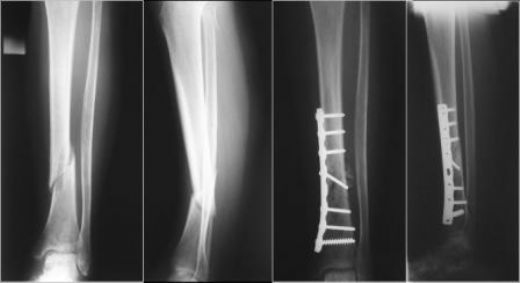

Konservatif tedavi, genellikle hafif kırıklarda tercih edilirken, cerrahi tedavi, kırığın kaynamasını sağlamak ve bacak fonksiyonunu geri kazandırmak amacıyla uygulanır. Platin Uygulamaları Kaval kemiği kırıklarında cerrahi tedavi seçeneği olarak platin kullanımı, kırığın stabilizasyonunu sağlamak için oldukça yaygındır. Platin, metal bir implant olup, kemiğin kaynamasına destek olur. Platin uygulamalarının avantajları arasında:

Sonuç Kaval kemiği kırığı, ciddi bir yaralanma olup, tedavi edilmediği takdirde uzun vadeli sorunlara yol açabilir. Platin uygulamaları, bu tür kırıkların tedavisinde etkili bir yöntem olarak öne çıkmaktadır. Erken tanı ve uygun tedavi ile hastaların iyileşme sürecinin hızlandırılması mümkündür. Bu nedenle, kaval kemiği kırığı belirtileri görüldüğünde mutlaka bir sağlık kuruluşuna başvurulması önerilmektedir. Ekstra bilgiler: Kaval kemiği kırıkları, sporcular arasında oldukça yaygındır. Özellikle futbol, basketbol gibi yüksek enerji gerektiren spor dallarında dikkatli olunması gerekmektedir. Ayrıca, osteoporoz hastalarının kemik sağlığını korumak amacıyla düzenli tıbbi kontroller yapmaları ve önerilen tedavi yöntemlerine uymaları önem arz etmektedir. |